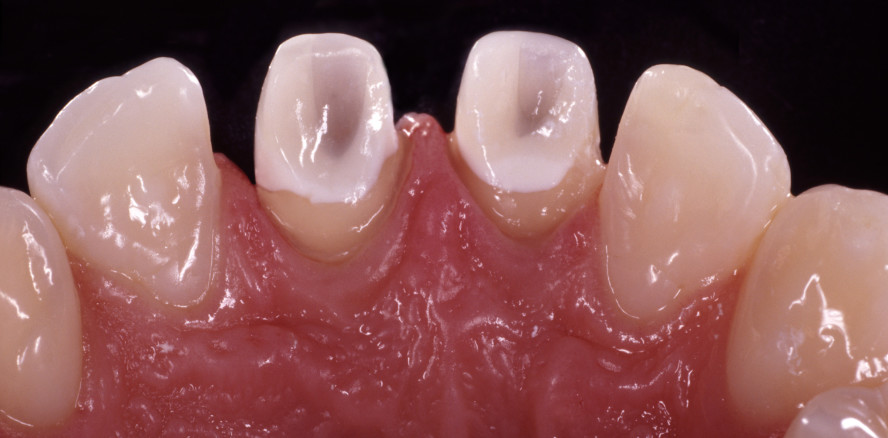

Ein 28-jähriger Patient stellte sich mit dem Wunsch vor, seine endodontisch behandelten und stark verfärbten mittleren Oberkiefer-Schneidezähne neu restaurieren zu lassen. Er gab an, seit der vor einigen Jahren durchgeführten Wurzelspitzenresektion keine Beschwerden mehr an den beiden Frontzähnen zu haben, beklagte jedoch die erheblichen ästhetischen Beeinträchtigungen, die durch das Erscheinungsbild seiner Zähne hervorgerufen würden (Abb. 1). Nach Auswertung des klinischen Befundes und des Röntgenbefundes wurden dichte und lege artis ausgeführte Wurzelkanalfüllungen an den Zähnen 11 und 21 diagnostiziert. Es waren keine Wurzelkanalstifte vorhanden. Die ausgedehnten Kompositfüllungen beider Zähne zeigten jedoch Undichtigkeiten und sich darunter entwickelnde Sekundärkaries (Abb. 2). Der Patient gab an, dass die Füllungstherapien der betroffenen Schneidezähne bereits mehr als fünf Jahre zurücklagen.

Nach Entfernung der temporären Versorgungen wurden die Präparationsflächen mithilfe von Reinigungsbürsten und einer fluoridfreien Reinigungspaste (Zircate, Dentsply Sirona) von Resten des Bondings befreit. Zur Kontrolle der Form- und Farbgebung wurden die Restaurationen mit einem eingefärbten Glyceringel einprobiert. Damit konnte bereits eine perfekte Maskierung der Pfeilerzähne erreicht werden, die sich in einem vom Untergrund unabhängigen einheitlichen Erscheinungsbild darstellte (Abb. 7).